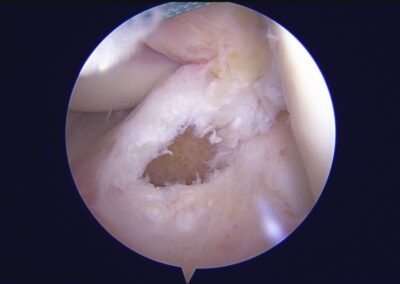

GalleryShoulder rotator cuff repair Meniscus root repair Meniscus repair Bankart repair for recurrent shoulder dislocation ACL reconstruction Machines Instruments